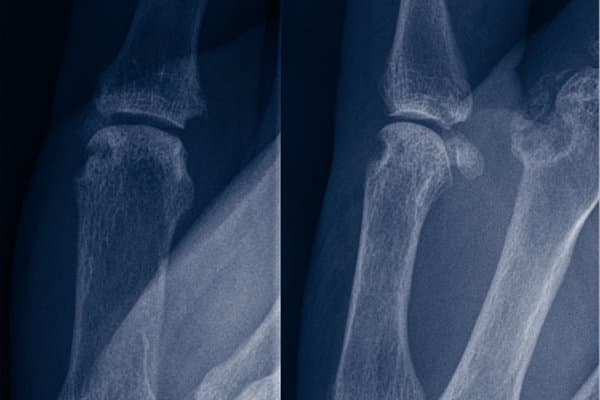

Il faut par exemple penser à une arthrite paranéoplasique chez les patients âgés en cas de début brutal de la maladie, de symptômes systémiques et de mauvaise réponse thérapeutique. L’arthrite à cristaux de pyrophosphate de calcium (PPC), aussi appelée chondrocalcinose, également fréquente chez les personnes âgées, présente aussi des points communs avec une polyarthrite rhumatoïde séronégative et constitue donc un diagnostic différentiel important.

En revanche, les patients atteints de PR séronégative ont un risque plus faible de lésions articulaires et osseuses que les patients séropositifs. Cela s’explique notamment par le fait que leur perte de masse osseuse est moins importante au cours des premières années qui suivent le début de la maladie.